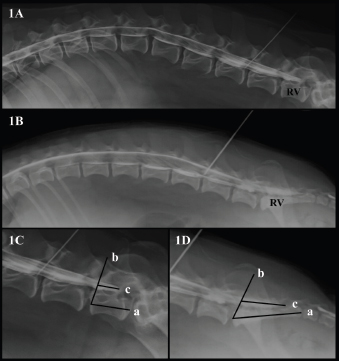

All myelographic studies were evaluated with commercially available DICOM digital image viewing software (Aycan, workstation v3.6). Only lateral radiographs could be evaluated, due to superposition with pelvic structures in the ventro-dorsal views. Four observers blinded to patient’s medical record information reviewed the studies that met the inclusion criteria. The observers annotated the vertebra where the DS ended (L6, L7/L8, or S1), and this vertebra was selected as a reference vertebra (RV) (Fig. 1A and B). The RV was measured longitudinally (at the level of the middle part of the vertebral body) in mm (Line a in Fig. 1C and D). The observers also measured the DS, and a percentage with respect to the RV measurement was calculated (%). To perform the measurements of the DS, a starting point was set drawing a line from the rostral midpoint epiphysis of the vertebral body of the RV to the caudal articular facet of the vertebra immediately rostral to it (Line b in Fig. 1C and D). The direction of the parallel line mimicked the insertion of a Tuohy needle during an epidural injection when L7 was considered the RV. From this line, the DS was measured in mm drawing a line parallel to the floor of the vertebral canal (Line c in Fig. 1C and D).

Fig. 1. (A). Canine lateral myelographic image where DS ends before the LS space. (B) Lateral myelographic image where the DS ends after LS space. (C) Measurement method used for the RV and DS ending where L7 was considered the RV. Line a=RV measurement. Line b=starting point for DS measurement. Line c=DS measurement. (D) Measurement method used for RV and the DS ending where the sacrum was considered the RV. Line a=RV measurement, Line b=starting point for the DS measurement. Line c=DS measurement.